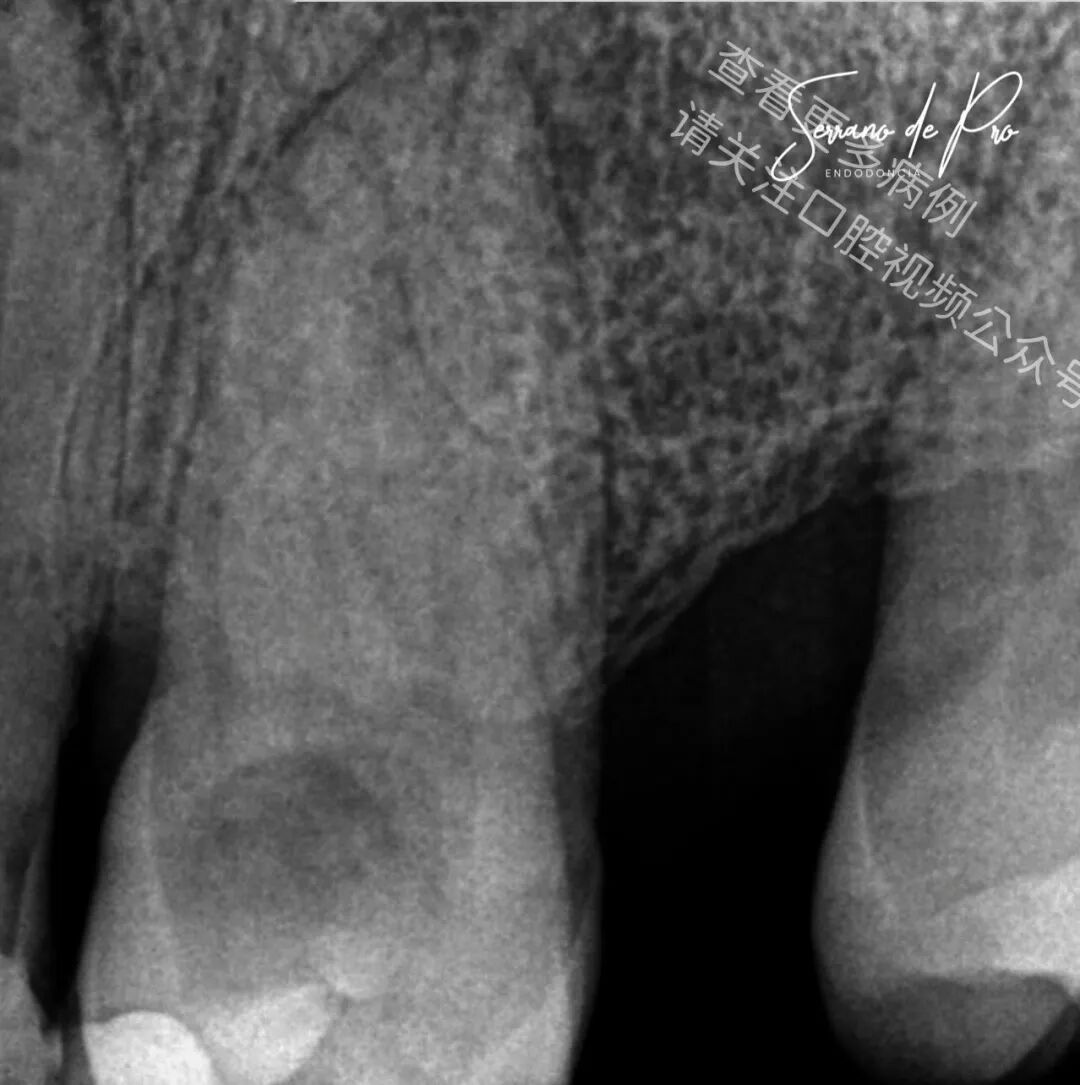

这是一个非常奇特的病例,24号牙和25号牙并非处于它们的正常位置,而是并排生长,拍出的X光片十分惊人。能如此清晰地看到根管充填的细节可不是每天都有的事。25号牙牙髓坏死,24号牙则患有严重的牙髓炎。

由于患者的病史,25号牙因存在禁忌证而未被拔除。